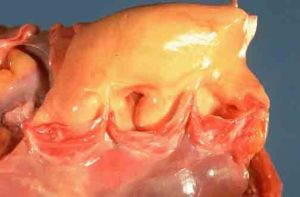

3.心臟 老年人心臟有退行性改變,心肌纖維的順應性減退,應激性降低,心肌舒縮功能和血排出量明顯降低,心臟指數(CI)降低,年齡越大CI 越低。心功能評定,我們推薦用紐約心臟病協會(NYHA)的4 級分級法。老年人常患有慢性肺心病、慢性心功能不全。遇有感染、創傷和心源性休克等誘因,可觸發心功能衰竭。如存在慢性缺氧、代謝性酸中毒、休克及CI 低於2.1L/m2 時,可確定診斷。